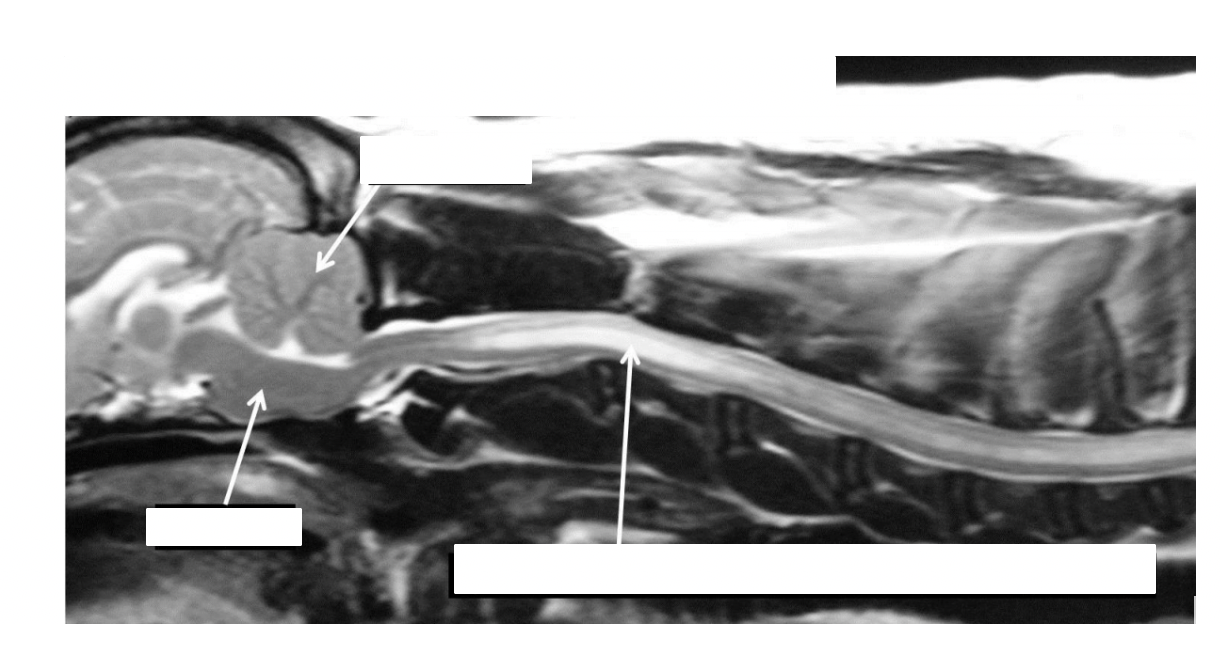

what are the structures shown

blue: interthalamic adhesion

red: brain stem

silver: spinal cord

identifty the interthalamic adhesion, brain stem, spinal cord